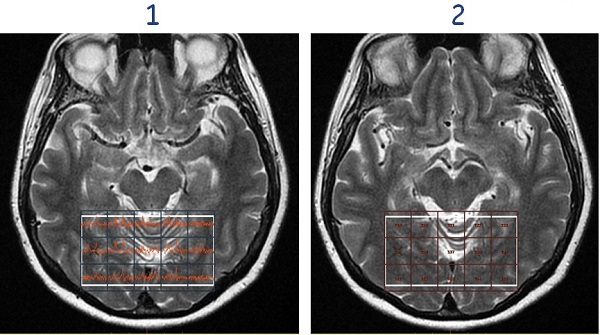

Figure 7. Show press box (1), Hide press box (2)

• Show/Hide sat bands toggles the SAT bands on and off.

Figure 8. Show SAT band (1), Hide SAT band (2)

• Show/Hide Spectroscopy voxels toggles the spectrum within each voxel on and off.

Figure 9. Show Spectroscopy voxels (1), Hide Spectroscopy voxels (2)

• Show/Hide Structural View toggles the spectrum and the voxel numbering within each voxel on and off the image.

Figure 10. Show Structural View (1), Hide Structural view (2)